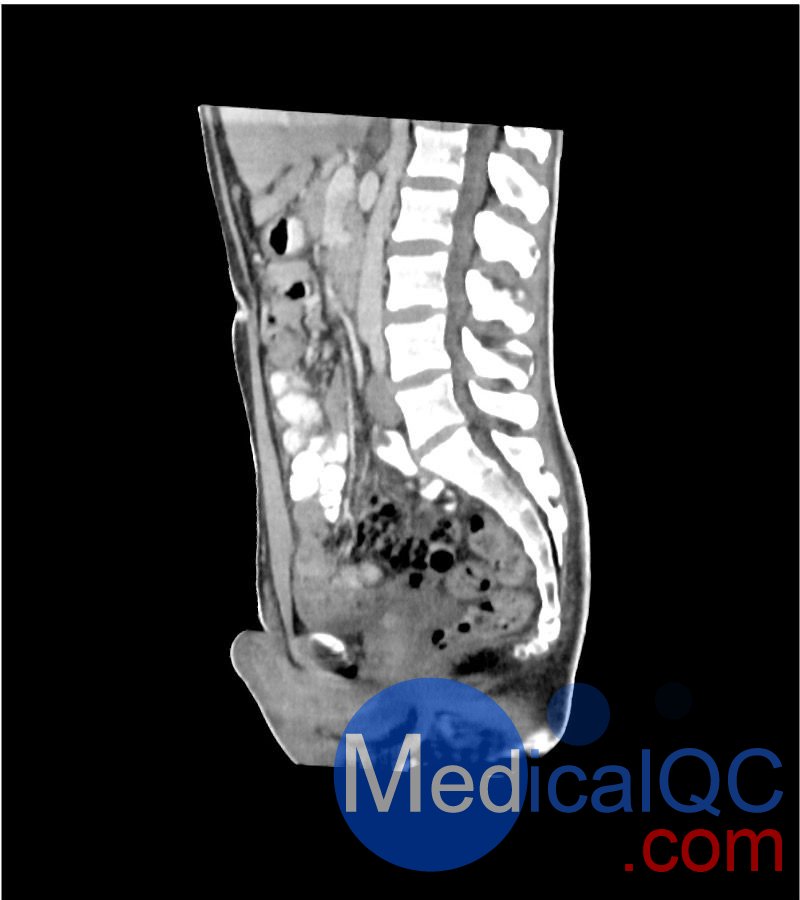

WEK-5501男性腹部模体,WEK-5501男性骨盘模体成像效果图:

WEK-5501男性腹部模体,WEK-5501男性骨盘模体

WEK-5501男性腹部模体,WEK-5501男性骨盘模体可模拟门静脉期的腹部和盆腔增强扫描效果,扫描范围覆盖第一腰椎至会阴区域。

该体模右侧设有髂淋巴结肿块(模拟病灶)。

1. 可对脉管系统、骨骼及软组织进行逼真模拟,涵盖的器官包括肝脏、胆囊、胰腺、脾脏、肾上腺、肾脏、胃、小肠、结肠、膀胱及前列腺。

2. 右侧设有髂外淋巴结肿块(模拟病灶)。